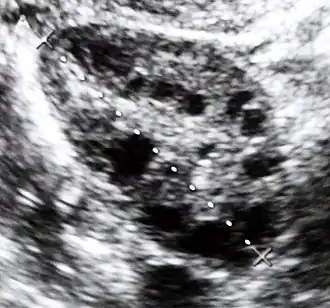

Examens morphologiques

L'échographie pelvienne montre des ovaires augmentés de volume avec un stroma épaissi. La cœlioscopie montre de gros ovaires lisses